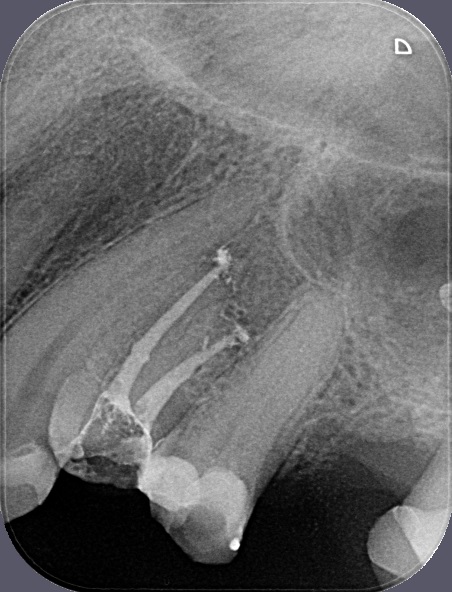

Porovnání průměrného ošetření způsobem plně hrazeným ze zdravotního pojištění (obrázek vlevo) a ošetření způsobem nadstandardním (obrázek téhož zubu po přeléčení vpravo) mohou přinést rentgenologické snímky níže.